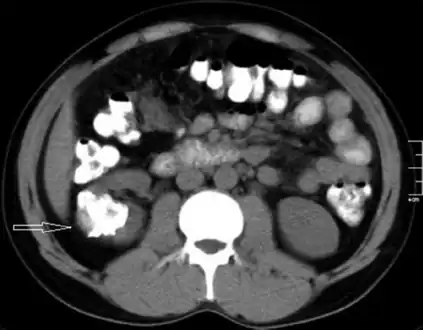

Left flank pain and gross hematuria diagnosed with renal medullary fibroma

Low mag.